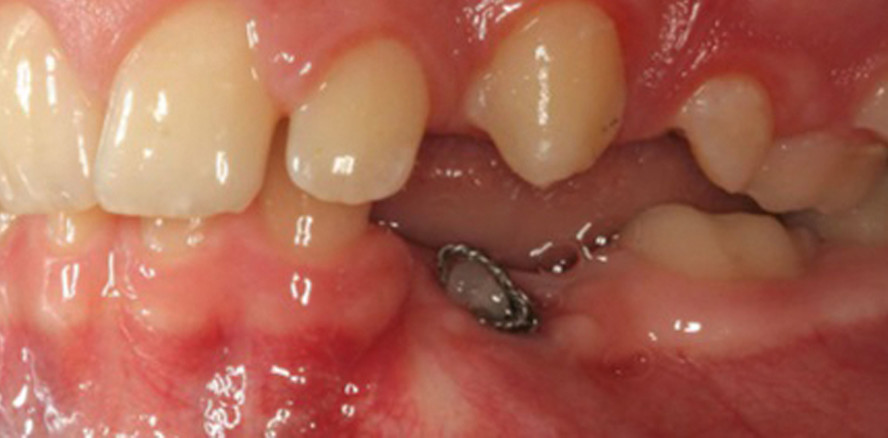

Therapie Nach ausführlicher Beratung und Abwägung aller Therapiealternativen erfolgte in enger Zusammenarbeit mit den behandelnden Kieferorthopäden im Jahr 2013 der operative Eingriff. Die Therapie bestand in einer Kombination aus verschiedenen chirurgischen Techniken. Zunächst wurden die Milchmolaren 55, 65, 75 und 85 extrahiert, die Zähne 13 und 33 anluxiert bzw. transplantiert und die Zähne 15 und 25 i. S. e. Ausgleichstransplantation zur Schaffung gleicher Zahnanzahlen in den jeweiligen Quadranten in den Unterkiefer in Regio 34 (25 > 34) und 45 (15 > 45) transplantiert. Der Eingriff erfolgte in allgemeiner Anästhesie. Die transplantierten Zähne wurden in Regiones 13, 33 und 34 in- traoperativ semirigide mittels 0,2 mm Titanium Trauma Splint (Medartis®) in Säure-Ätz-Technik (Bleach flow, Ivoclar Vivadent®) an ihren Nachbarzähnen eingeschient. Aufgrund der Wurzelmorphologie des Zahns 43 konnte das Transplantat in Regio 45 nicht in approximalen Kontakt zu Zahn 43 gestellt werden. Das Risiko einer iatrogenen Verletzung der Zahnwurzel 43 durch Schaffung der Neoalveole musste ausgeschlossen werden. Das Transplantat Regio 45 konnte somit nicht mit einer TTS-Schienung in Position gehalten werden, sondern wurde mit einer Überknüpfnaht vor Aspiration gesichert (Abb. 2).

Die Entfernung des Titanium Trauma Splints erfolgte jeweils drei Wochen postoperativ. Dadurch konnte der nächste Behandlungsschritt freigegeben werden und der Patient wurde zur weiteren Therapie an die behandelnde Kieferorthopädie zurücküberwiesen. Es folgte die kieferorthopädische Ausformung von Ober- und Unterkiefer mit Einstellung des transplantierten Zahns 13. Zahn 14 ist noch retiniert und befindet sich aktuell im Durchbruch. Mittels herausnehmbarer Apparaturen durch laufende kieferorthopädische Behandlung zeigte sich der Verlauf drei Monate post OP (Abb. 3a und b). Um eine vollständige Rehabilitation zu gewährleisten, wurde darauf hingearbeit^et, dass die Schaltlücken Regiones 15, 24, 35, 44 im Sinne eines folgenden implantologischen Lückenschlusses im Erwachsenenalter offengehalten wurden. Nach inzwischen fünfeinhalb Jahren post operationem ist der kieferorthopädische Behandlungsverlauf deutlich zu sehen (Abb. 4a und b). Der etwas hypoplastische Zahn 14 hat inzwischen auch den physiologischen Durchbruch erreicht und kann in die kieferorthopädische Therapie miteinbezogen werden. Im weiteren Verlauf wurden die Lücken 15, 24, 35, 44 für eine spätere Implantation vorbereitet. Es folgte nun die kieferorthopädische Retentionsphase. Der Patient ist mittlerweile 21 Jahre alt und für die anstehende dentale Implantation mit definitiver prothetischer Versorgung vorbereitet. Das Knochenlager stellt sich röntgenologisch und klinisch in orovestibulärer und in vertikaler Dimension im Ober- sowie im Unterkiefer für eine Implantation als ausreichend dar.